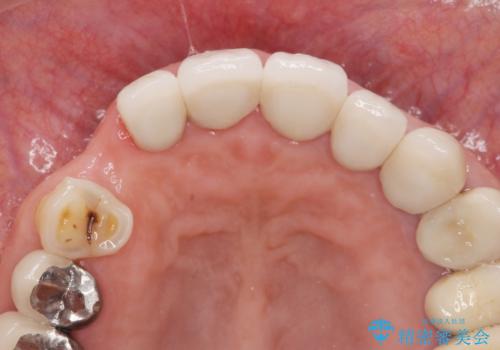

クラウン下に再発した深い虫歯 インプラントによる機能回復

- 定期検診で通院されていたところ、20年前に他院で治療した前歯のセラミック歯の下に深い虫歯が再発していることがわかりました。

- 45万円(ストローマンインプラント・骨造成・チタンカスタムアバットメント・ジルコニアクラウン)費用は治療当時の料金となります